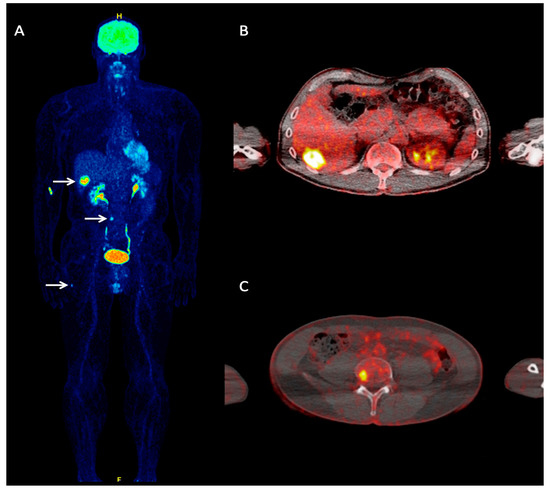

- Winkler, J.; Dimitrakopoulou-Strauss, A.; Sachpekidis, C.; Enk, A.; Hassel, J.C. Ipilimumab has efficacy in metastatic Merkel Cell Carcinoma: A case series of five patients. J. Eur. Acad. Dermatol. Venereol. 2017, 31. [Google Scholar] [CrossRef]

- Eshghi, N.; Lundeen, T.F.; MacKinnon, L.; Avery, R.; Kuo, P.H. 18F-FDG PET/CT for Monitoring Response of Merkel Cell Carcinoma to the Novel Programmed Cell Death Ligand 1 Inhibitor Avelumab. Clin. Nucl. Med. 2018, 43, e142–e144. [Google Scholar] [CrossRef] [PubMed]

- Vellani, C.; D’Ambrosio, D.; Licata, L.; Vacchieri, I.; Bernardo, A.; Trifirò, G. Monitoring response of advanced Merkel cell carcinoma to Avelumab with 18F-FDG PET/CT. Eur. J. Nucl. Med. Mol. Imaging 2018, 46, 1197–1198. [Google Scholar] [CrossRef] [PubMed]